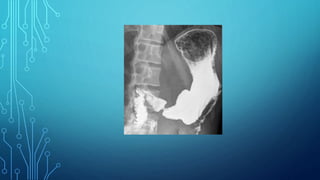

6. Fluoroscopy of the stomach: the main

symptoms are filling defect, the presence of

aperestaltic zones. Apithetic relief of the

mucous membrane, local thickening or

breakage of the folds of the mucous membrane.

Diagnostics 1. Complaints 2. Anamnesis 3.Palpation 4. Study of gastric contents 5. Blood test 6. Fluoroscopy of the stomach: the main symptoms are filling defect, the presence of aperestaltic zones. Apithetic relief of the mucous membrane, local thickening or breakage of the folds of the mucous membrane. 7. Gastroesophagoduodenoscopy 8. Biopsy